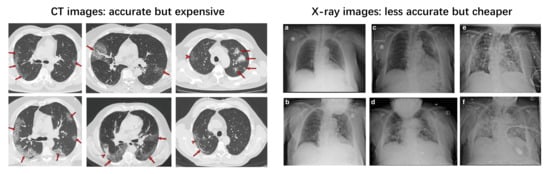

2. Input Modalities: CT or X-ray

2.1. Clinical Perspective

2.2. Artificial Intelligence Perspective